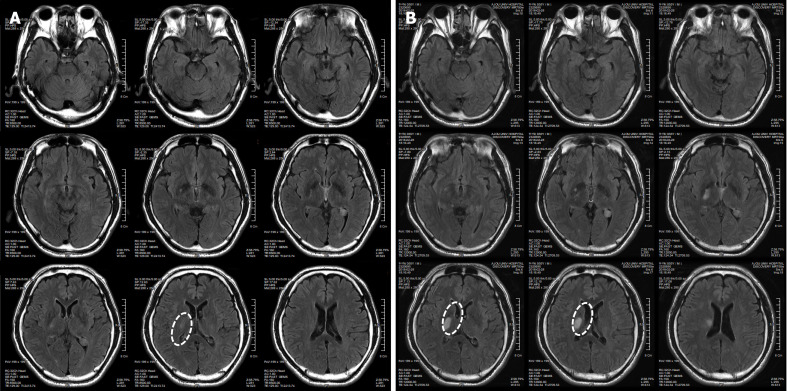

患者在干細胞移植后約30個月拍攝腦部CT圖像以確認病灶的大小。病灶縮小至0.6cm×0.3cm(圖4)。

圖4:微創人臍帶間充質干細胞移植后患者的腦部計算機斷層掃描圖像。

圖4